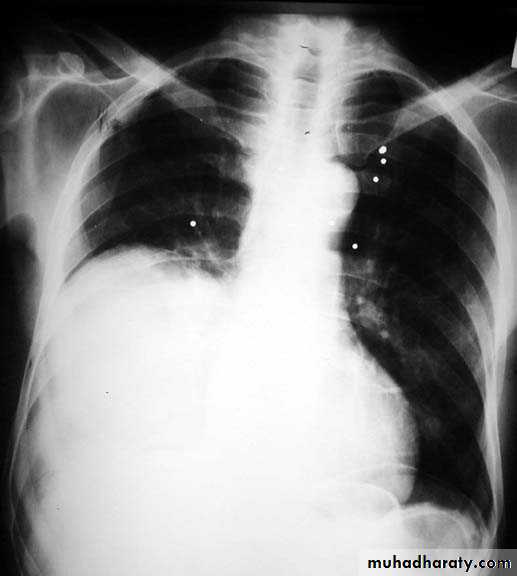

Pleural effusion ( free)

Massive pleural effusion